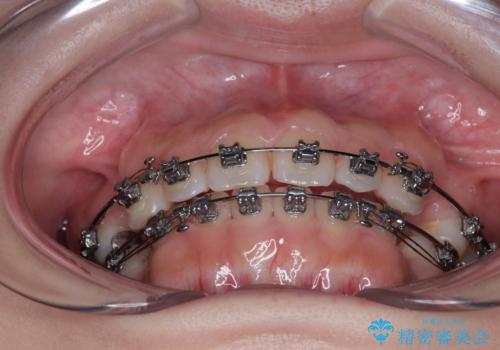

- メタルブラケット

- 2年2ヶ月

- 10-30回

しかしながら、唇を閉じたときに口元に緊張感があり、そのまま叢生を解消すると横顔が突出した印象になる可能性が高かったため、上下左右の小臼歯4本を抜歯して、ワイヤー装置にて矯正治療を行うこととしました。

矯正治療後には、目立っていた奥歯の銀歯をオールセラミッククラウンへ作り替え、スッキリした口元に仕上がりました。